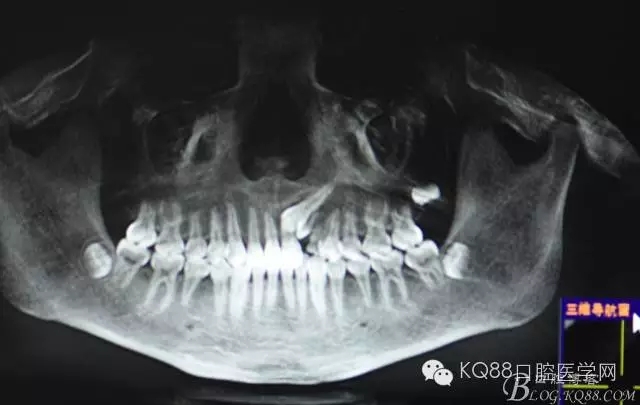

圖2.全景片影像檢查:23牙冠的遠(yuǎn)中還有一顆22畸形牙、及63滯留